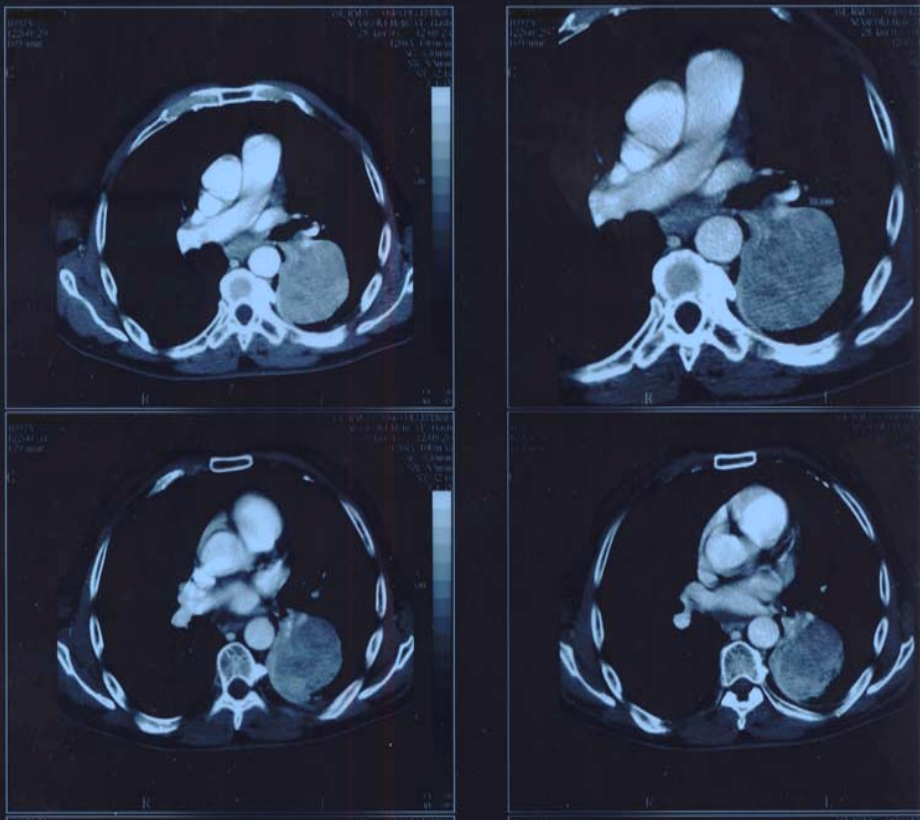

Figure2